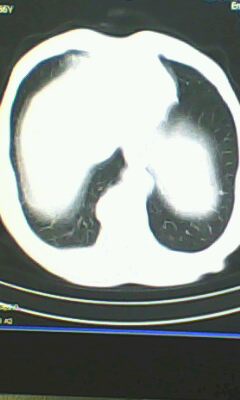

标题: CT26182:男 胸憋 无其它异常症状

胸廓呈桶状,双膈低平,肺实质及纵隔未见明显异常密度灶考虑肺气肿.

肺气肿

以下是引用ctkz987在2010-5-5 21:30:00的发言:[br]胸廓呈桶状,双膈低平,肺实质及纵隔未见明显异常密度灶考虑肺气肿.

弥漫性肺气肿 但内胆管轻度扩张

临床诊断:copd